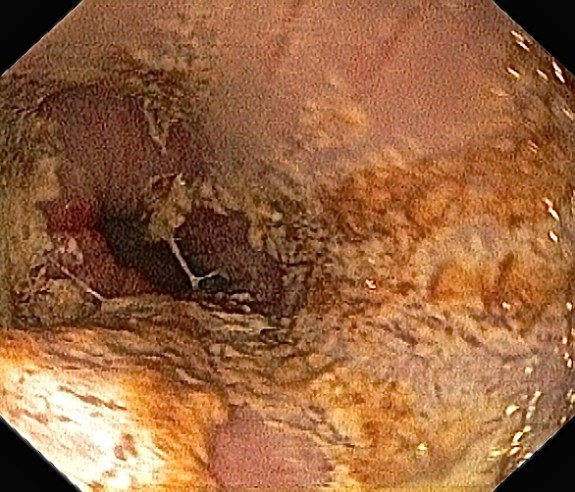

Omtrent samme bilde som ovenfor, tatt av meg tidligere. Bildet viser øsofagitt (betennelse i slimhinnene i spiserøret) forårsaket av hyppig oppkast, refluks av magesyre og overvekst av sopp og bakterier.

Mer spiserør.